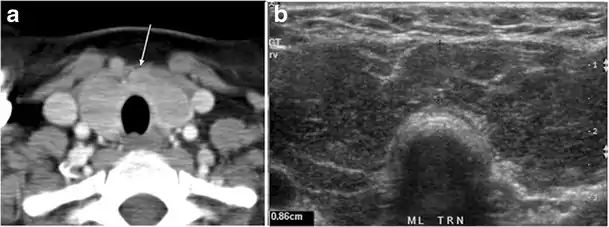

Fig. 4. A 45-year-old male patient presented with anterior mediastinal metastatic PTC lesions and occult primary on imaging. Histopathology examination of the resected thyroid gland revealed micro-foci of PTC; the largest, in the isthmus, measured 4 mm. a transverse greyscale ultrasound of the thyroid demonstrates homogeneous gland with normal echogenicity and size. No focal lesion or micro-calcifications. b Non-enhanced CT scan obtained as part of PET/CT examination shows a heterogeneous, large, relatively dense anterior mediastinal mass (white arrow) with peripheral calcification (arrowheads). Thyroid gland has normal CT appearance with no abnormal FDG uptake (not shown).[1]

Fig. 7. A 51-year-old female patient post total thyroidectomy for PTC with elevated thyroglobulin measurement. an Axial non-enhanced CT scan of the neck at the level of the thyroid bed demonstrates a well-defined, rounded, homogenously dense soft tissue situated between the trachea and left internal jugular vein (white arrow). b Transverse ultrasound image of the neck demonstrates a well-defined, homogeneous, hypoechoic soft tissue nodule measuring 6 mm (white arrow) with no detected micro-calcifications. Biopsy showed a predominantly residual normal thyroid tissue with micro-foci of PTC.[1]